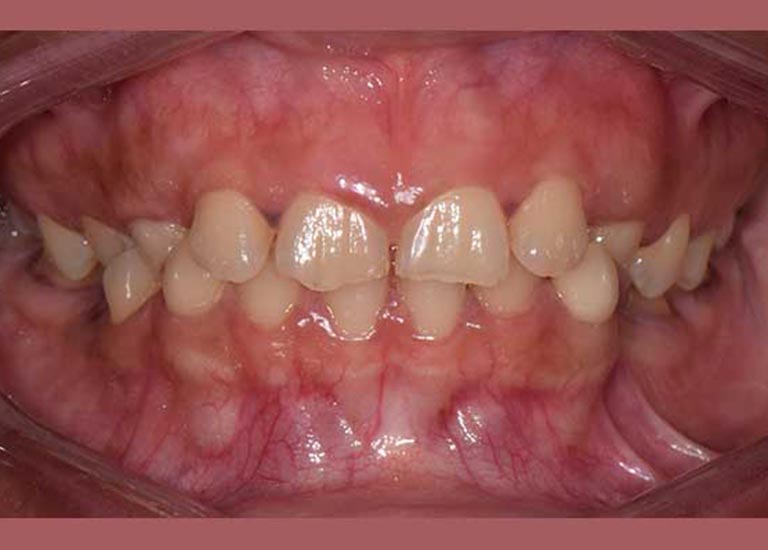

راجعتني هذه السيدة وهي تعاني من مشاكل معقدة؛ فأنيابها العلوية الدائمة لم تبزغ أبداً، وبقيت الأنياب اللبنية في مكانها. بالإضافة إلى ذلك، كانت أنيابها السفلية بازغة للداخل، مما سبب لها صعوبات كبيرة في الأكل والنطق وأفقدها الثقة بابتسامتها لدرجة أنها رفضت تصويرها في البداية.

كما تظهر الصور، كانت النتيجة تحولاً جذرياً. تم سحب جميع الأسنان المنطمرة ورصفها في مكانها الطبيعي، وتم تصحيح وضع الأسنان السفلية. في نهاية العلاج، طلبت السيدة بنفسها وبكل ثقة أخذ صورة لابتسامتها الجديدة التي طالما حلمت بها.